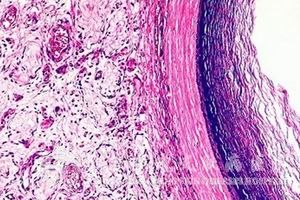

表皮囊肿是一种怎样的病症?很多人对此都不了解,为了让大家对该症有个很好的了解,我们就请北京京城皮肤医院来为大家进行简单的病症说明。

专家称,表皮囊肿的病程是比较长久的,其病情发展十分缓慢,因此,尽管其肿瘤体积较大,但是患者所表现出来的临床症状却是比较轻微的。